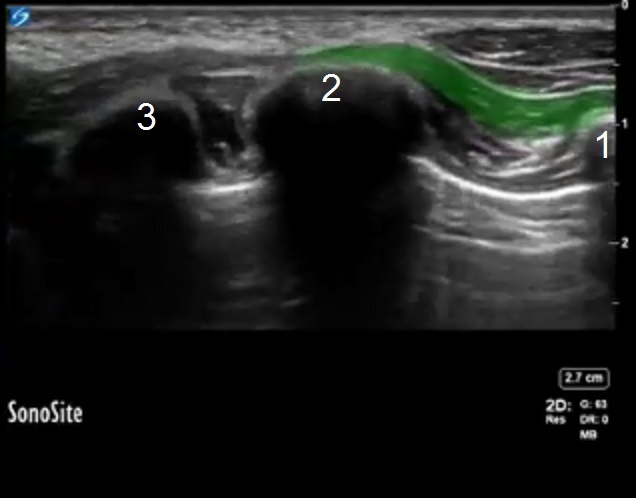

鋸の解剖学 1 画像

強調表示された領域: 前鋸筋

第 4 肋骨

第 5 肋骨

第6肋骨